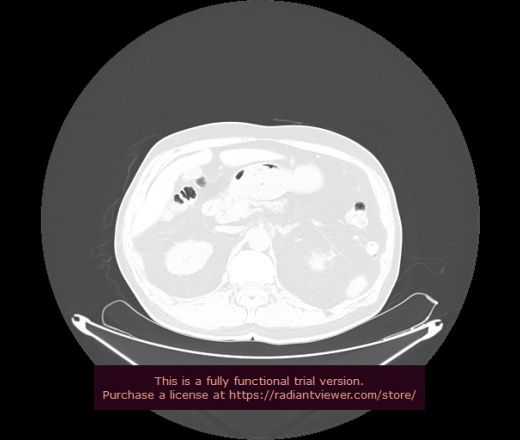

Уважаемые коллеги, если имеется интерес, сможете ли Вы спрогнозировать дальнейшее +-одинаковое течение процесса у 4 данных разных пациентов? Зацепиться где-то можно очень просто, где-то нельзя.